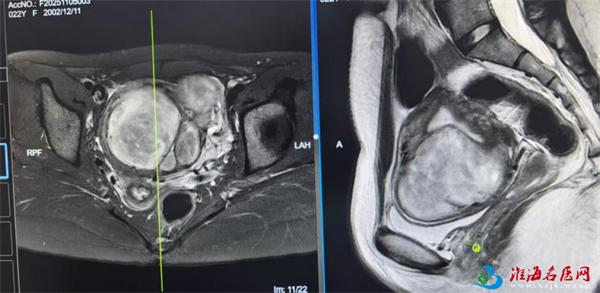

患者核磁 影 像

近日,徐州市妇幼保健院妇科十五区肿瘤亚专科蔡莉主任团队接诊到一名子宫肌瘤患者,术中竟从其体内取出30多枚子宫肌瘤,腹腔镜画面触目惊心!更令人震惊的是——这位22岁的患者不仅未婚,竟连性生活史都没有!

当腹腔镜下看到子宫的那一刻,连从业多年的蔡主任都倒吸冷气:密密麻麻的肌瘤如同葡萄串般挤满子宫!这场持续2小时的微创手术,成功拆除埋在花季少女体内的"定时炸弹"。